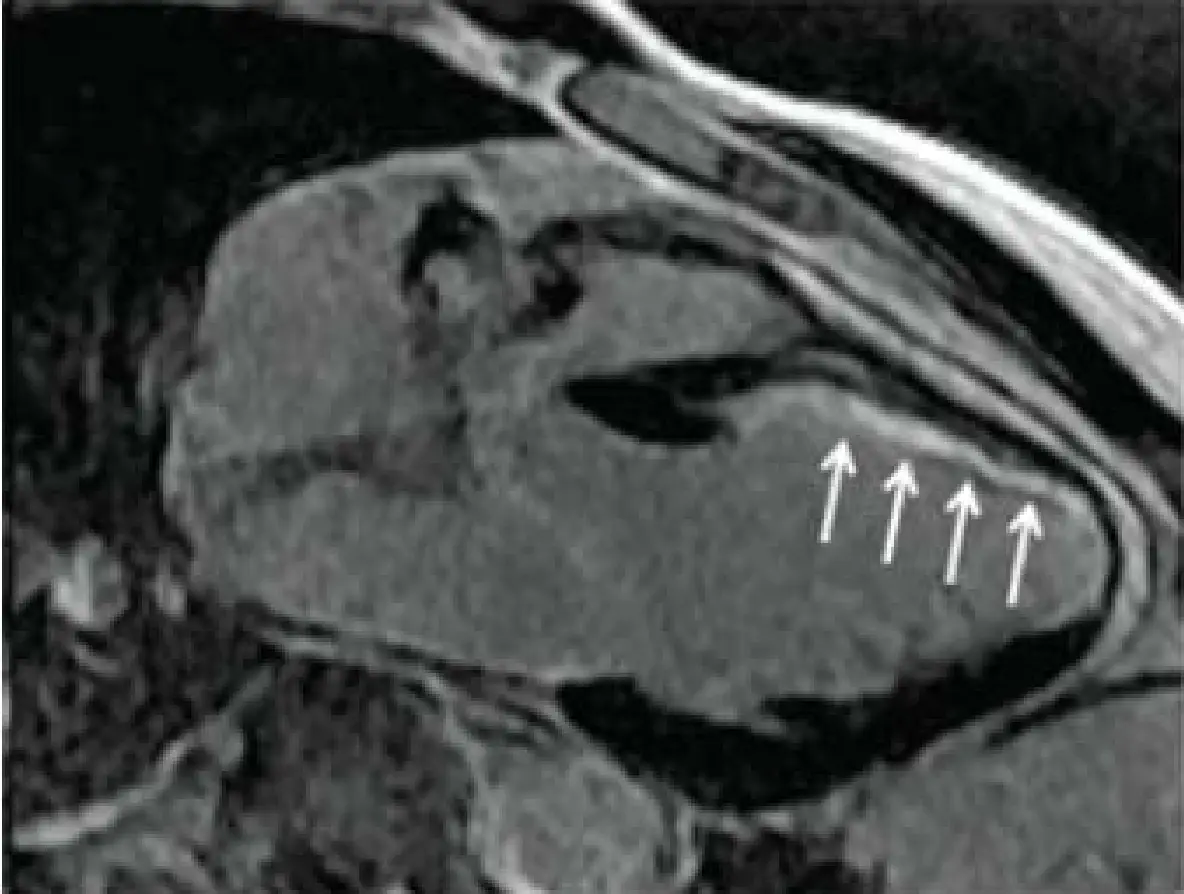

承上題【一位70歲女性病患胸痛1小時到急診,過去病史有高血壓與高血糖;但血壓控制不良,至急診時血壓為160/100毫米汞柱,糖化血色素最近數值為8.0%,最近無出血傾向或上消化出血紀錄,血氧飽和濃度(SpO₂) 為98%.聽診心臟無S3奔馬音,肺部聽診無濕囉音(moist rales)或喘鳴音(wheezing),四肢皮膚溫暖且下肢無水腫,心電圖與胸部X光片如圖一及圖二。請問下列敘述何者為是? 】,該名病患於出院後3個月心臟超音波左心室射出分率 (LVEF)為25%,血清肌酐酸為1.1 mg/dl,血清電解質無異常,爬一層樓梯不到便會發生胸悶跟動喘,在2週後發生到院前喪失生命徵狀(out of hospital cardiac arrest),經送至急診回復生命跡象與意識,住院後做了心臟核磁共振掃描(late gadolinium enhancement)如附圖。有關這位病人的處理,下列何者不正確?

- 心臟核磁共振(LGE):長軸截面可見心內膜下(subendocardial)局部強烈對比劑滯留,說明該處為陳舊性梗塞疤痕(scar),瘢痕周邊易成為電生理異常迴路的基質。

選項A:病人除顯著LVEF下降外,MRI上可見subendocardial scar,這類梗塞疤痕是VT/VF的基質,能誘發心室頻脈或心室顫動,導致猝死。此敘述正確。